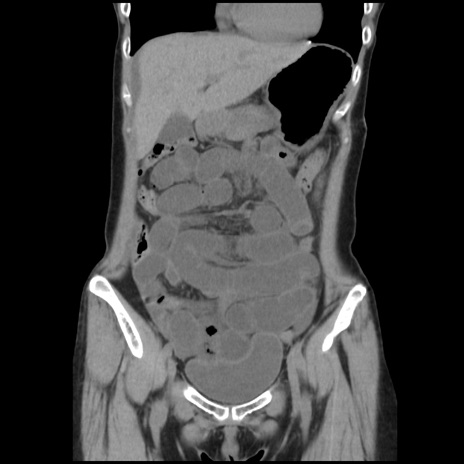

症例32(冠状断像)

【症例】40歳代 女性

【主訴】上腹部痛、嘔気・嘔吐

【現病歴】約9時間前頃から急に上腹部痛、嘔気、嘔吐が出現。改善しないため救急要請。

【既往歴】子宮頚癌(広汎子宮全摘術、放射線療法)、腸閉塞

【身体所見】腹部:平坦、軟、腸雑音亢進、上腹部を中心に腹部全体に圧痛あり。

【データ】WBC 8400、CRP 0.03